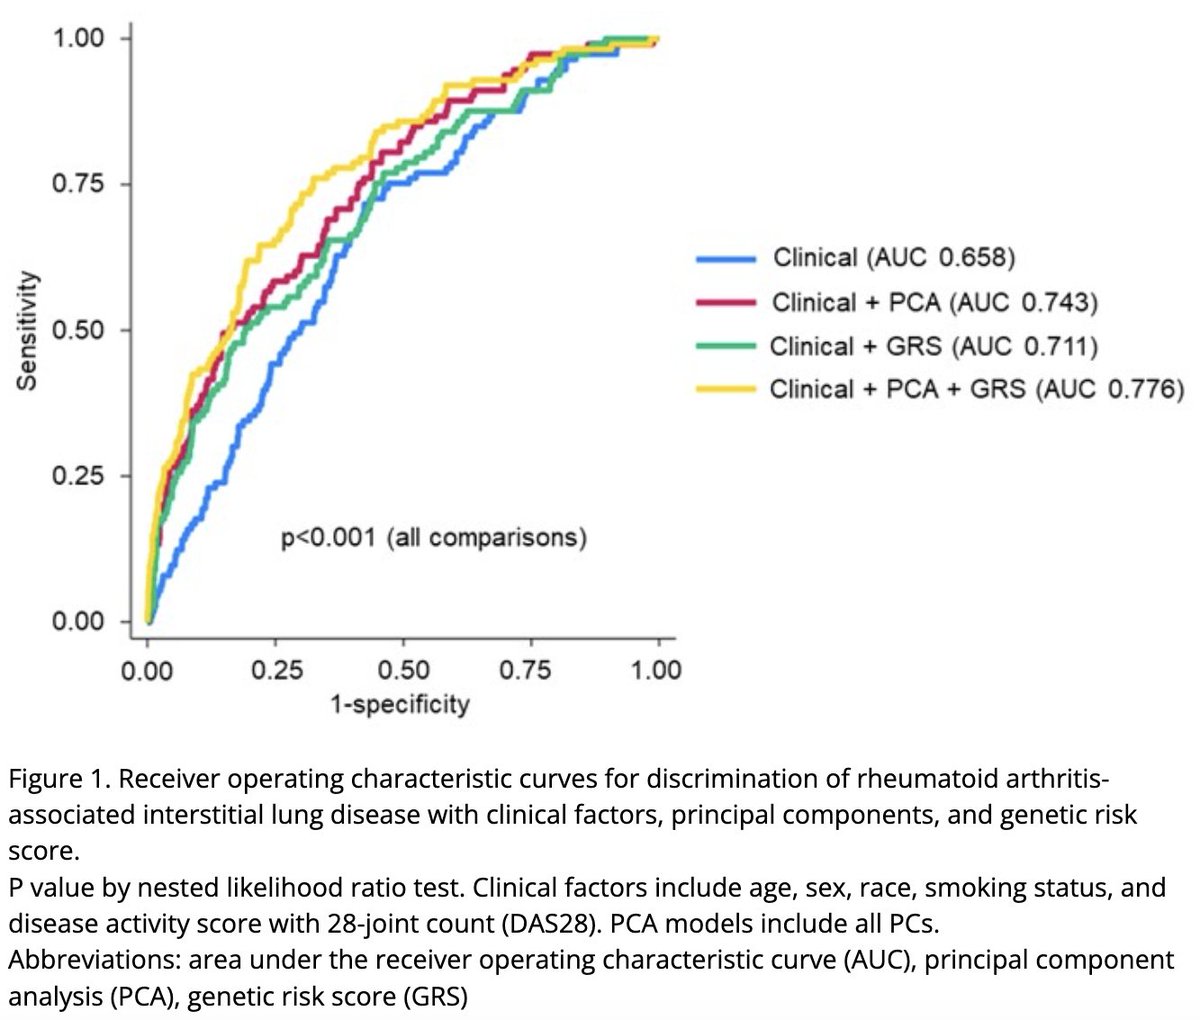

Can we predict who will develop #RA-#ILD?

Wheeler et al showed a combination of genetic risk score, peripheral protein #biomarkers & clinical risk factors can help identify RA-ILD in RA patients.

Does this bring us closer to #PersonalisedMedicine?

Ab0799 #ACR24 @RheumNow https://t.co/JZkJNGmLM1

Mrinalini Dey DrMiniDey ( View Tweet)